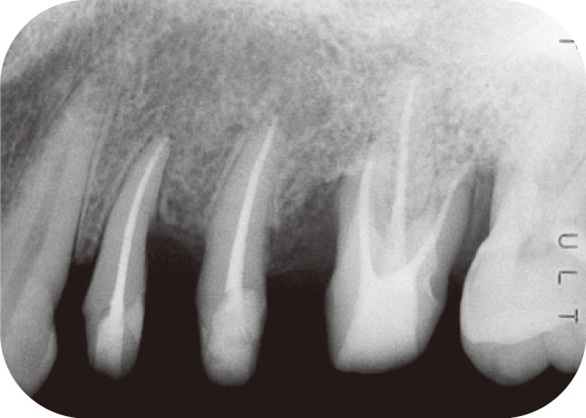

症例2:症例は43歳女性で、初診では#11遠心に10mm、#21近心に9mmの歯周ポケットがあり、#11遠心より排膿が認められたもので、重度歯周疾患の症例である(図3)。

デンタルX線写真(図4)では根尖近くまで達する明瞭な垂直性骨吸収が認められる。

図4 症例2のデンタルX線写真。